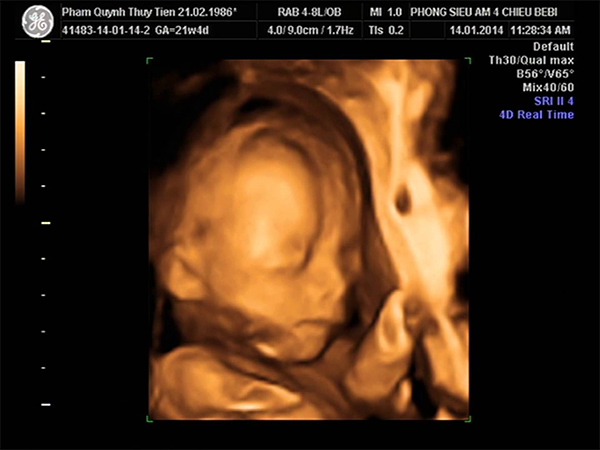

Khi bé được 22 tuần tuổi thì sẽ có kích thước tương tự một quả bí, chiều dài từ mông đến đỉnh đầu ước chừng khoảng 28cm và khối lượng vào khoảng 453gr. Hình dáng của bé lúc này đã có nhiều nét của trẻ siêu âm, mẹ đã có thể nhìn thấy các đường nét rõ ràng trên khuôn mặt bé qua hình ảnh siêu âm. Bác sĩ sẽ chỉ cho mẹ nhìn thấy phần lông mày và mí mắt của bé đang dần hoàn thiện.

Lúc này, qua hình ảnh siêu âm thì làn da của bé vẫn khá nhăn nheo và được phủ một lớp lông tơi, sẽ mất một thời gian nữa thì nó mới căng mịn.